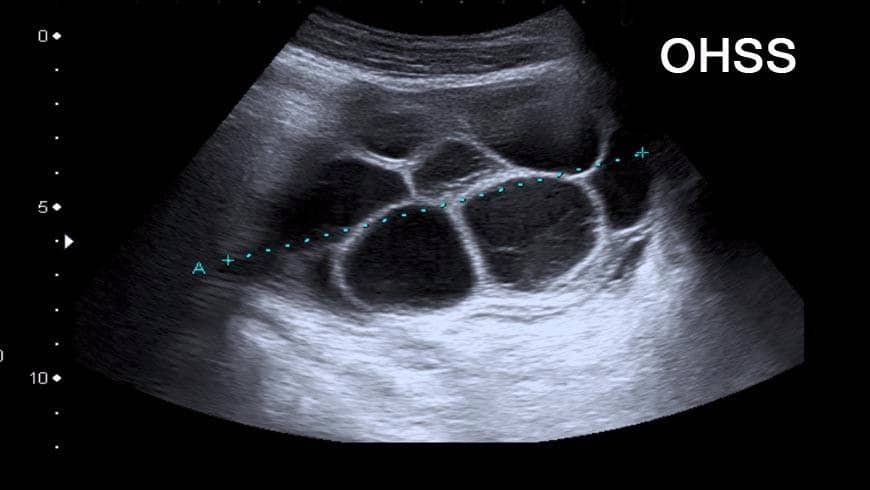

Ovarian hyperstimulation syndrome (OHSS) hay Hội chứng quá kích buồng trứng (QKBT) xảy ra khi buồng trứng bị kích thích quá mức và tăng kích thước do sử dụng thuốc điều trị vô sinh (hoặc hiếm gặp do đột biến của thụ thể FSH).

QKBT đặc trưng bởi cảm giác trướng bụng khó chịu, tăng kích thước buồng trứng và có dạng nang, xuất hiện dịch màng bụng.

QKBT mức độ vừa

Các đặc điểm lâm sàng bao gồm đặc điểm của QKBT nhẹ cộng với bằng chứng siêu âm của dịch ổ bụng. Tăng kích thước buồng trứng lên đến 12 cm trong chiều dài nhất của chúng. Khó chịu ở bụng và các triệu chứng tiêu hóa (ví dụ, buồn nôn, nôn và tiêu chảy) thường xuyên và nặng hơn so với QKBT nhẹ.

Chẩn đoán QKBT bằng tiền sử lâm sàng và siêu âm qua ngả âm đạo, cần có tiền sử kích thích buồng trứng và sau đó là xét nghiệm hCG.